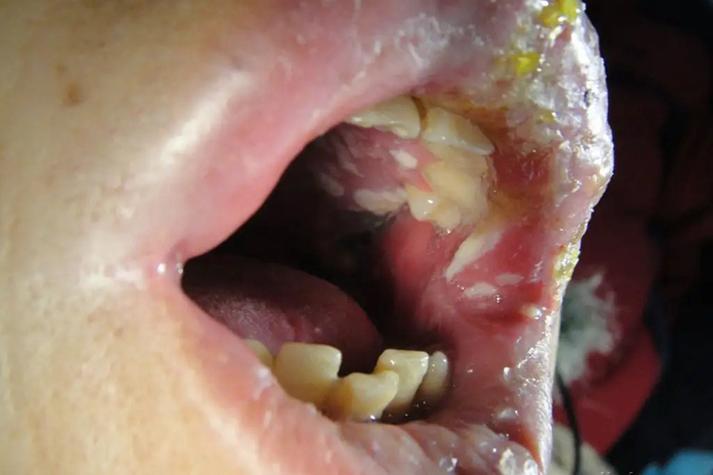

- 口腔黏液腺囊肿: 这是最常见的原因之一,我们的上颚黏膜下分布着许多微小的唾液腺,当腺体的导管被堵塞时,分泌的唾液就会形成一个充满液体的小囊肿,看起来就像透明或半透明的小泡泡,它们通常是柔软的,不痛,但有时可能会因为咀嚼等动作而破裂。

- 疱疹性口炎: 由单纯疱疹病毒引起,初期可能只是上颚等部位出现成簇的小水疱,这些水疱很快会破溃,形成表浅的小溃疡,并伴有疼痛、灼热感、发烧、淋巴结肿大等症状,这是最常见的病毒性口腔溃疡之一。

- 扁平苔藓: 一种原因不明的慢性炎症性口腔黏膜病,病损可以表现为白色条纹、网状结构,也可能出现一些小丘疹或水疱,疱破后会形成糜烂面,通常没有自觉症状,或有时有轻微的刺激痛。

- 天疱疮: 这是一种比较严重的自身免疫性疾病,非常罕见,典型特征是口腔和皮肤上出现松弛的、易破的水疱,疱壁很薄,破溃后形成大面积的、不易愈合的糜烂面,疼痛剧烈,如果您怀疑是这个,请务必立即就医。